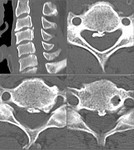

[画像診断]後縦靱帯骨化症(OPLL)について